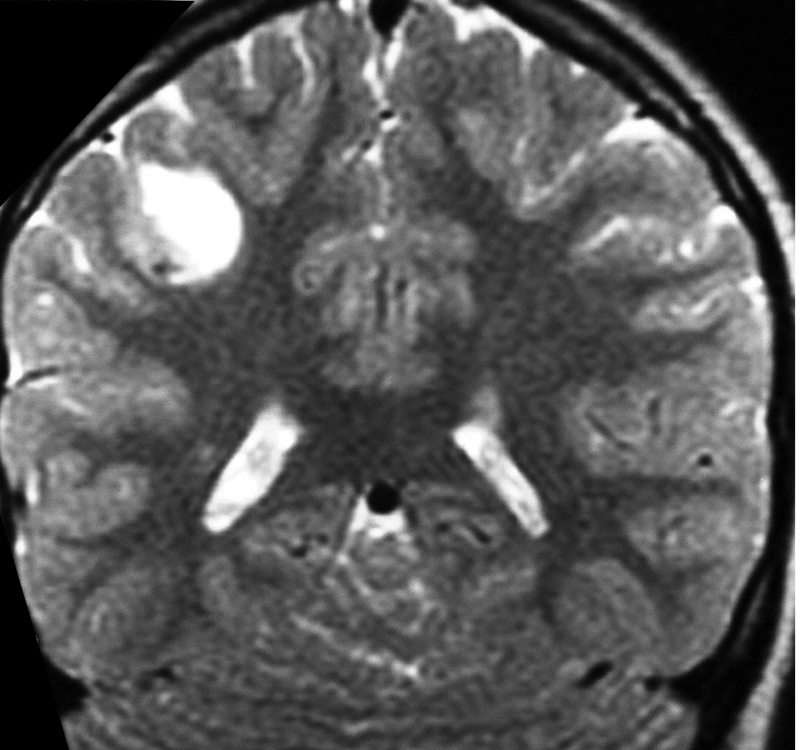

Imaging of a ganglioglioma

The images show a CT, T2-weighted and FLAIR image of a ganglioglioma, with a cystic component and an enhancing mural nodule, seen on the contrast CT image.

• Either a partly cystic abnormality, with an enhancing mural nodule or a solely solid abnormality (which may expand an overlying gyrus)

• Solid components that are iso- or hypointense on T1-weighted images and hyperintense on T2-weighted images

• A distinct absence of peritumoral edema (on T2-weighted images/FLAIR)